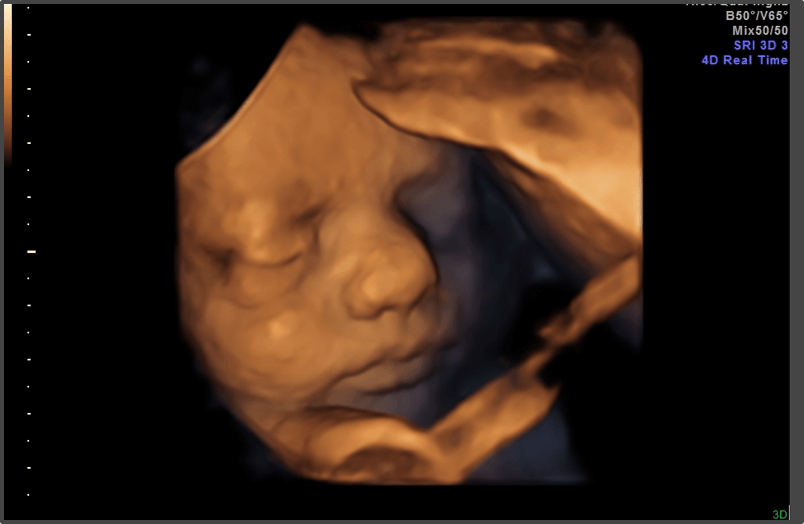

Your baby is the size of a cantaloupe.

Approx Baby Weight: 2.1kg

Approx Baby Size: 45 cm

Baby Development

The baby’s lungs are continuing to mature, and it is now preparing for life outside the womb.